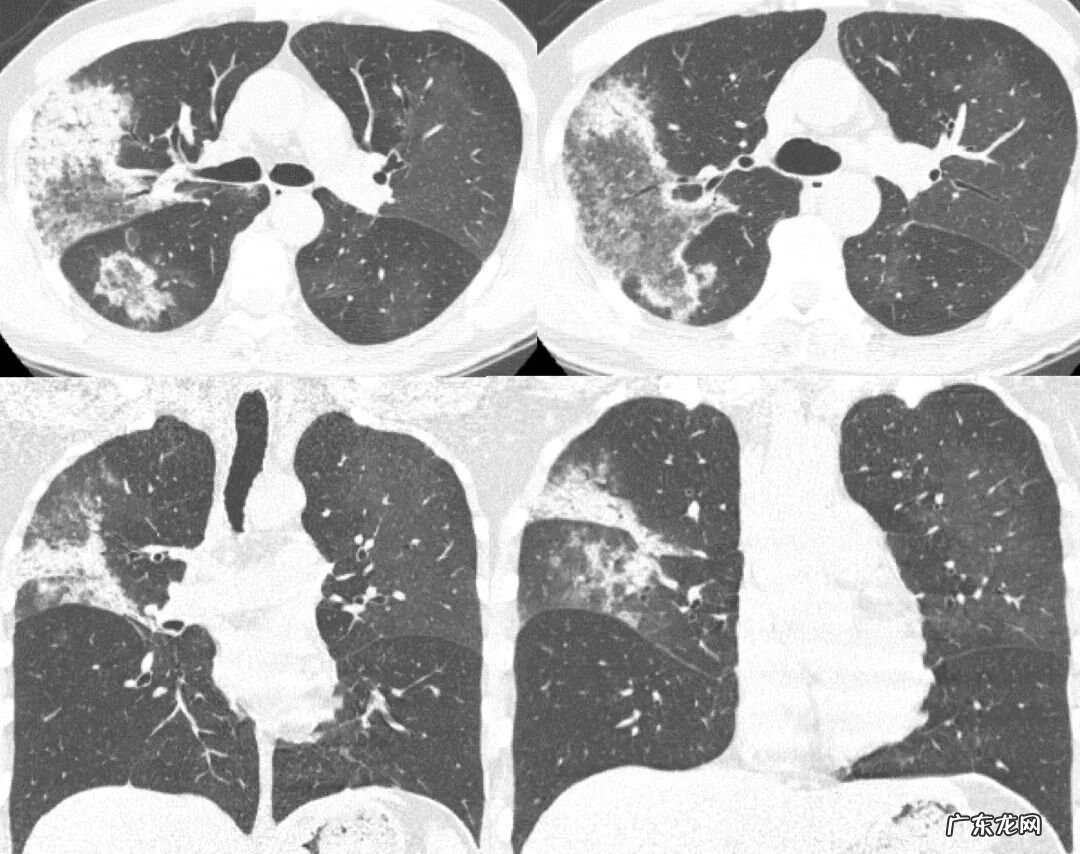

反晕征并非OP的特征性表现,在很多疾病中(肺结核,ANCA相关血管炎,结节病,PCP)都可以出现,需要影像表现的细节信息及临床资料建议鉴别 。

VS 肺结核

肺结核是一大类容易出现反晕征的改变,它的反晕征的周围实变影其实不是实变,是肉芽肿性结节堆积造成的,形状不规则,边缘结节感较强,磨玻璃中心可见结节影,同时伴有支气管壁增厚,树丫征,周边可见磨玻璃密度的渗出影,但是渗出影往往也可以看到结节 。这与OP不同,OP中间的磨玻璃影很少出现结节 。此外,除了反晕征,肺结核还有其他的影像,如空洞,硬结灶,钙化灶,临床多有结核中毒症状 。